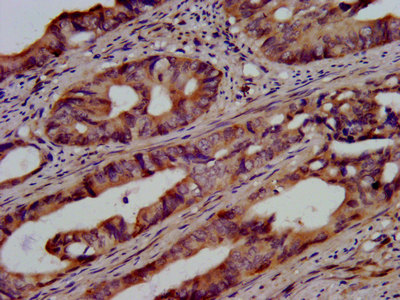

IHC image of CSB-PA025453LA01HU diluted at 1:500 and staining in paraffin-embedded human colon cancer performed on a Leica BondTM system. After dewaxing and hydration, antigen retrieval was mediated by high pressure in a citrate buffer (pH 6.0). Section was blocked with 10% normal goat serum 30min at RT. Then primary antibody (1% BSA) was incubated at 4°C overnight. The primary is detected by a biotinylated secondary antibody and visualized using an HRP conjugated SP system.

IHC image of CSB-PA025453LA01HU diluted at 1:500 and staining in paraffin-embedded human pancreatic cancer performed on a Leica BondTM system. After dewaxing and hydration, antigen retrieval was mediated by high pressure in a citrate buffer (pH 6.0). Section was blocked with 10% normal goat serum 30min at RT. Then primary antibody (1% BSA) was incubated at 4°C overnight. The primary is detected by a biotinylated secondary antibody and visualized using an HRP conjugated SP system.